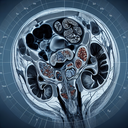

МРТ органів черевної порожнини

Магнітно-резонансна томографія (МРТ) органів черевної порожнини – це неінвазивний метод діагностики, який використовує магнітні поля і радіохвилі для створення детальних зображень внутрішніх органів. МРТ допомагає отримати чітке уявлення про структуру і стан органів без використання рентгенівських променів. ### Коли проводять МРТ черевної порожнини: - **Детекція патологій печінки, селезінки, підшлункової залози, нирок, жовчного міхура...